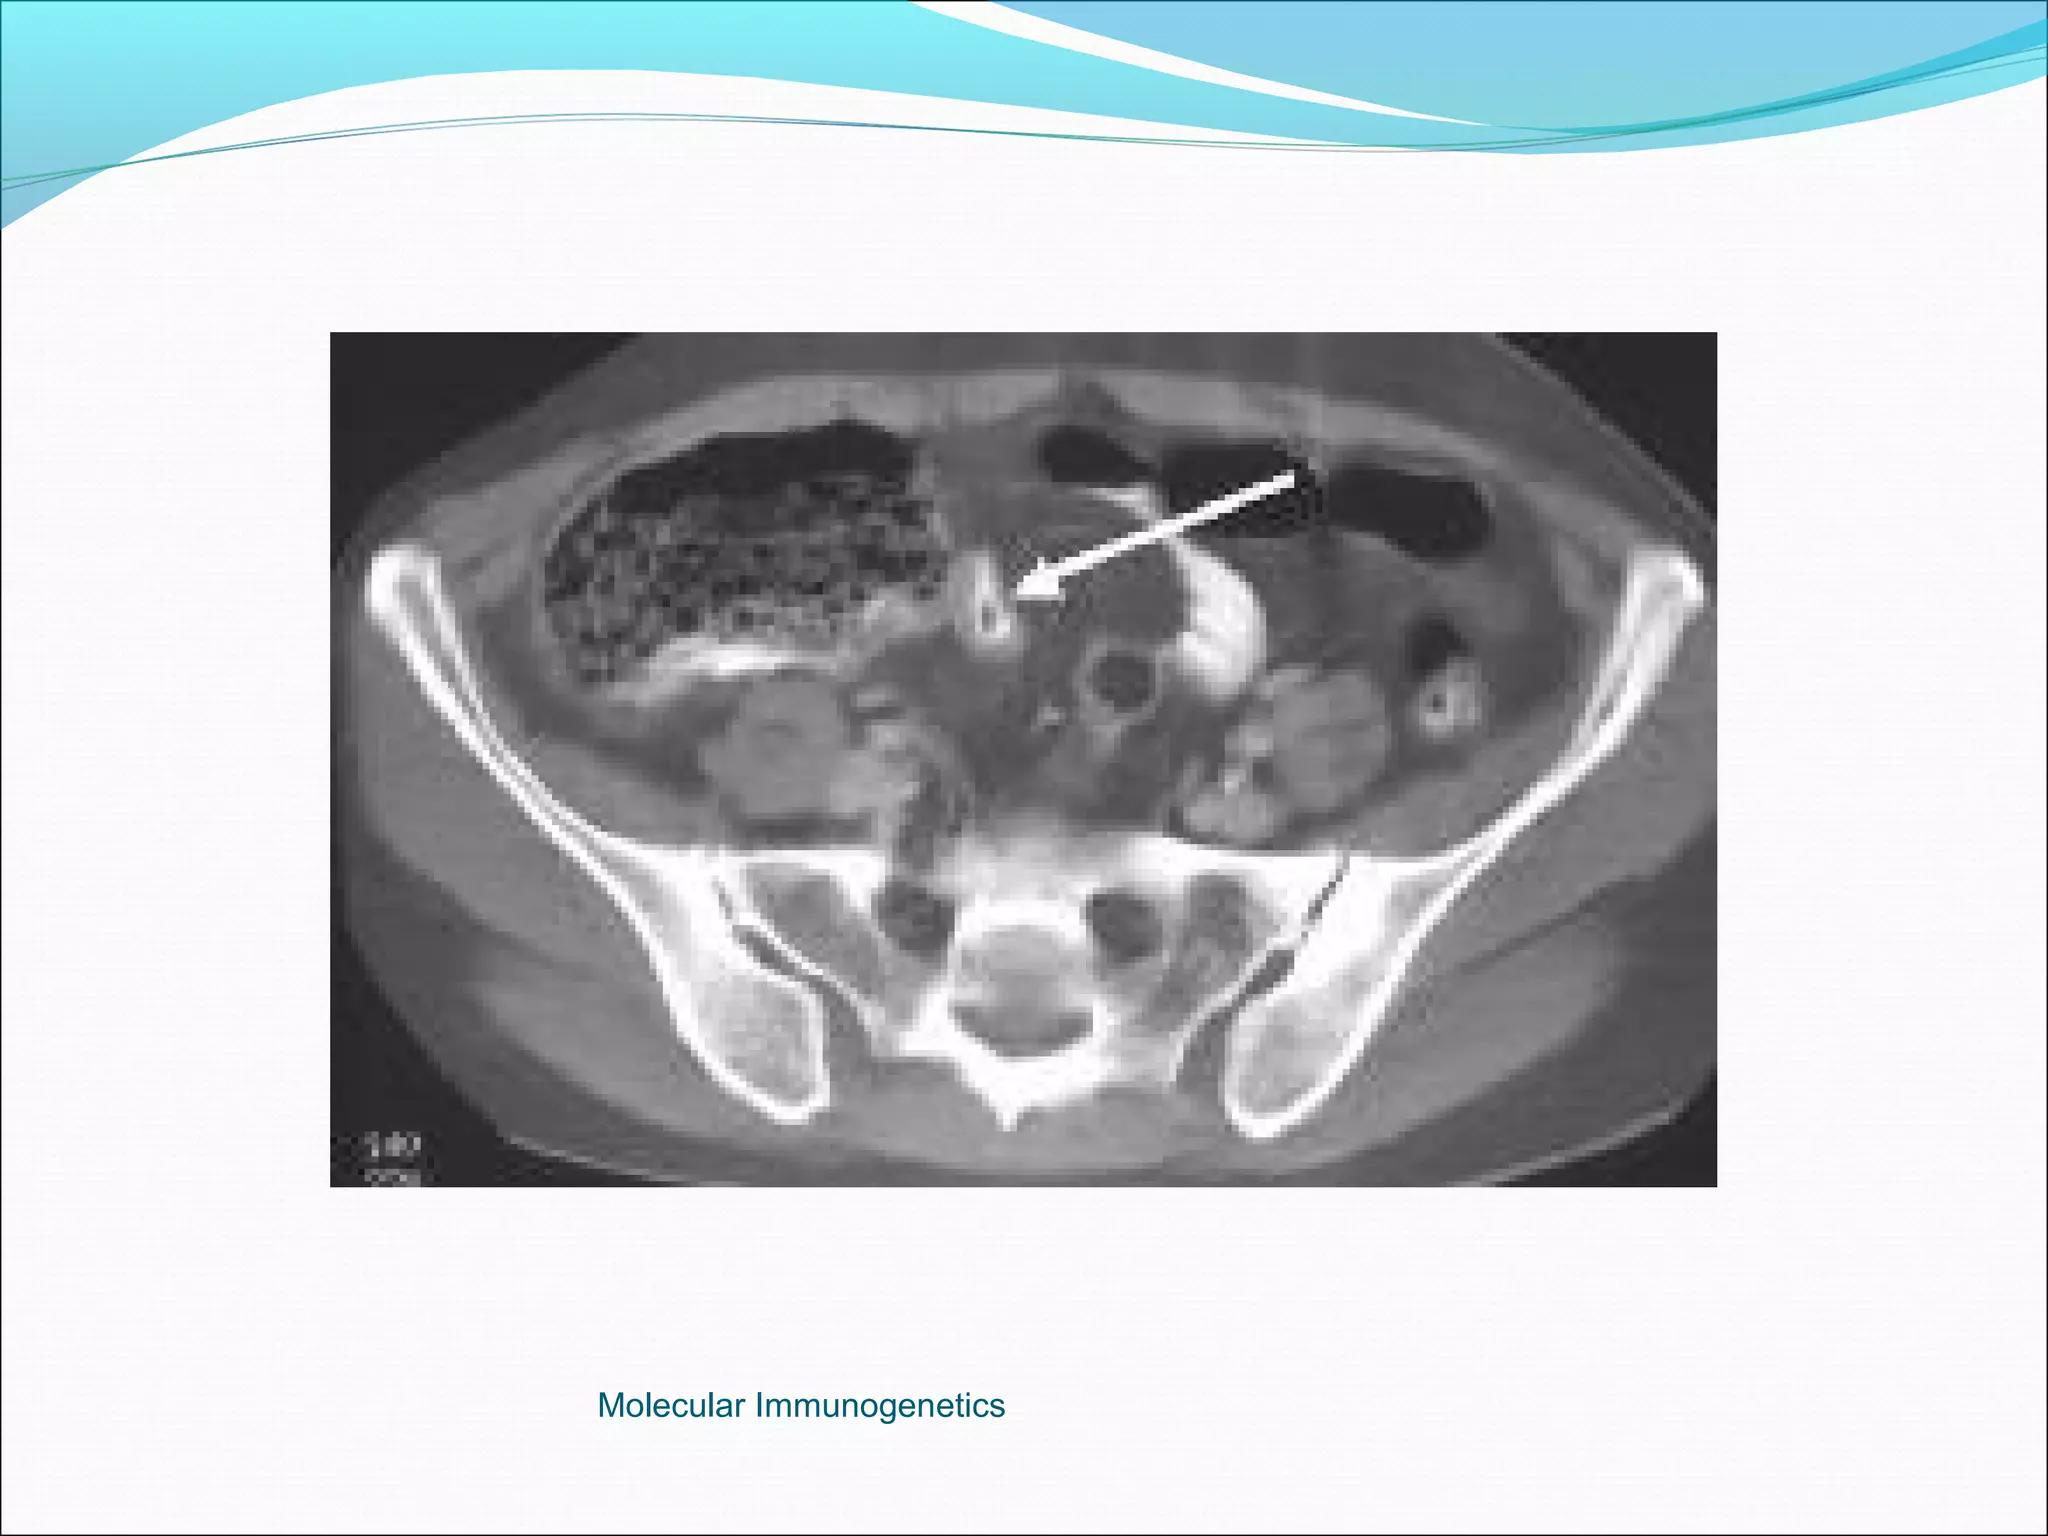

Ultrasound highly sensitive (80-90%), excludes

Computer Tomography: More superior to USS in diagnostic accuracy.